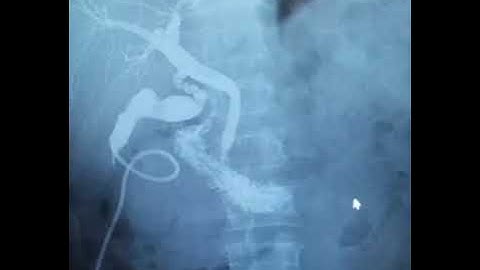

Intra-operative cholangiogram